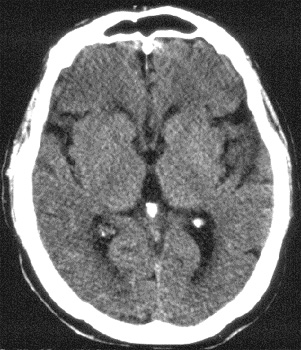

Head CT > Stroke > CT of Subacute Infarction

CT of Subacute Infarction

CT of a subactue infarction has the following findings in 1 -3 days:

- Increasing mass effect

- Wedge shaped low density

- Hemorrhagic transformation